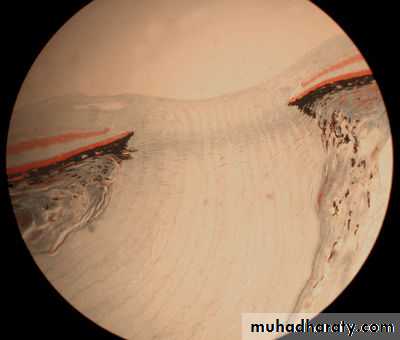

Sclera

Cornea

Canal of Schlemm

A higher magnification of the Corneoscleral junction showing the trabecular meshwork and the canal of SchlemmTrabecular meshwork

A section through the sclera just lateral to the corneoscleral junction, conjunctival epithelium(CjEp), conjunctiva(Cj),stroma of the sclera(S), and the canal of Schlemm(CS)